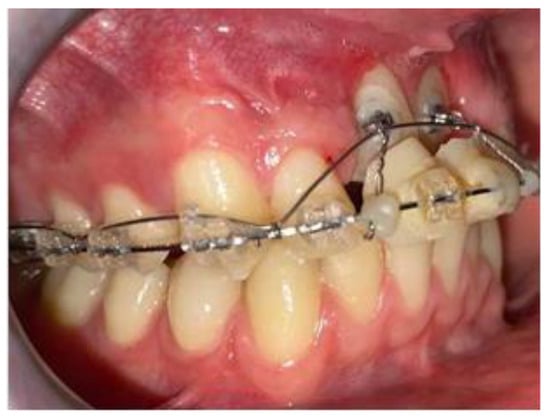

2. Case Report

2.2. Clinical Exams and Diagnosis

2.3. Therapeutic Plan

3. Results